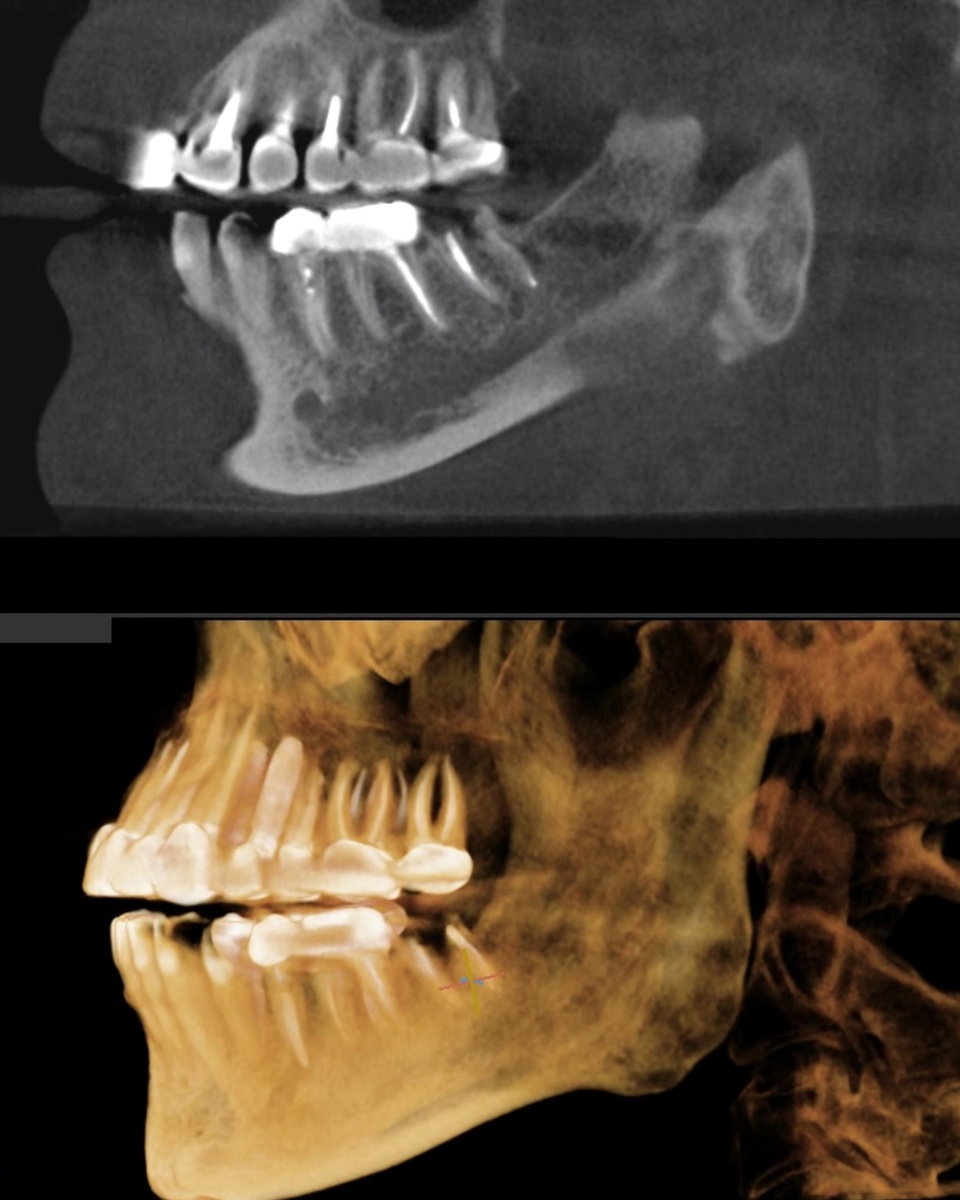

На самом-то деле, этот клинический случай - праздник для хирурга. То, что мы увидели на КТ (выше скрин) и во рту, порадовало!

• Костная ткань - в отличном состоянии. Достаточный объём по высоте и ширине, никакой атрофии. Это значит, что никакой костной пластики не будет, можно избежать дополнительных операций и месяцев ожидания .

• Десна - шикарная, толстенькая, отличная. Такая десна хорошо заживает, красиво формируется вокруг коронки, меньше рисков рецессии в будущем, больше защиты для имплантата.

• Зуб-антагонист (верхний зуб, который смыкается с нижним) - не сместился, не опустился. Это важно - когда зуб долго отсутствует, верхний начинает «выдвигаться» вниз, занимая пустое пространство. Здесь этого не произошло и для будущей коронки места достаточно.

Планирование имплантации в цифровом протоколе

По классике жанра - сделали компьютерную томографию с пазухами и суставами, сделали цифровой слепок, загрузили всё в программу планирования. Виртуально «примерили» разные имплантаты, посмотрели, как они встанут в кость, как будет выглядеть будущая коронка. Распечатали шаблоны хирургические.

И вот на этапе планирования стало понятно, что здесь идеально подходит одномоментная имплантация. Удаляем корни и сразу в лунку ставим имплантат. Один визит, одна анестезия и операция, один период заживления.

Смотрите, в чём проблема. Корни у зуба 3.7 были большие - значит, лунка после удаления получается широкая. При этом при всём, корни анатомически располагались близко друг к другу - костная перегородка между ними не самая мощная.

Что это значит на практике? Стандартный имплантат Nobel (да и любой другой) в такой широкой лунке не получил бы достаточной первичной стабильности. Он бы просто «болтался» в кости, не за что было бы зацепиться - перегородка тощая, не удержит.